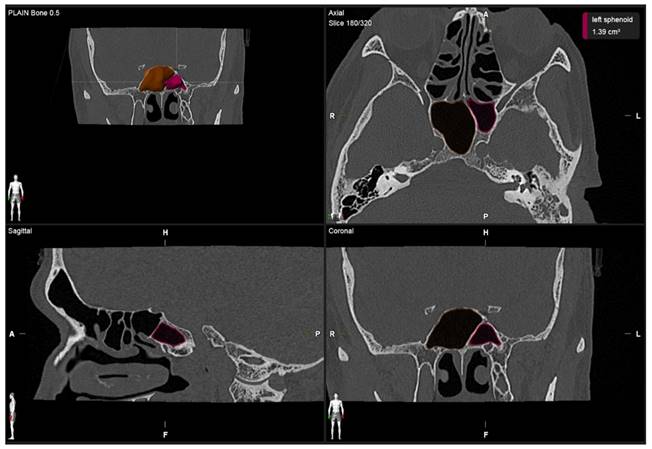

A single investigator, an otolaryngologist with more than ten years of clinical experience, performed image segmentation by measuring the volume of the sphenoid sinus. For each patient, the volume of the sphenoid sinus was measured using commercial real-time segmentation software (Elements SmartBrush, Brainlab AG, Munich, Germany) on a personal computer. The software exploits parallel implementation of a sparse field level-set solver on the Graphics Processing Unit (GPU) by implementing the level-set algorithm and has been utilised in various clinical applications such as tumour localisation and estimation of tumour dimensions [15,16]. The segmentation was achieved using a set of Hounsfield units in CT. The anatomical volumetric measurements were performed by means of this software in hand tracing. The lumen of the sinus was delineated. The lumen of the sinus was defined as the space within the bony walls of the sinus in all three planes (axial, coronal, and sagittal) (Figure 1). Within an automatically determined region of interest (ROI), segmentation was conducted by the 3D interpolation of the program itself. The software uses an inverse present method. The program reconstructs a 3D model of the sinus from the DICOM image sequence on which the volume was selected by cutting out the complementary areas of the air-filled area in the three dimensions manually; then, the volume was reconstructed and measured in cubic centimetres (cm3) by the software (Figure 2). Each side of the sphenoid sinus (right and left) were measured separately. The total sphenoid sinus volume was obtained based on the right and left sphenoid sinus volume summation. After 15 days, the measurements were repeated. All information was analysed using Statistical Package for Social Sciences (SPSS) software version 26.0.

Figure 2

3D reconstruction in the sphenoid sinuses in all planes (sagittal, axial, and coronal).